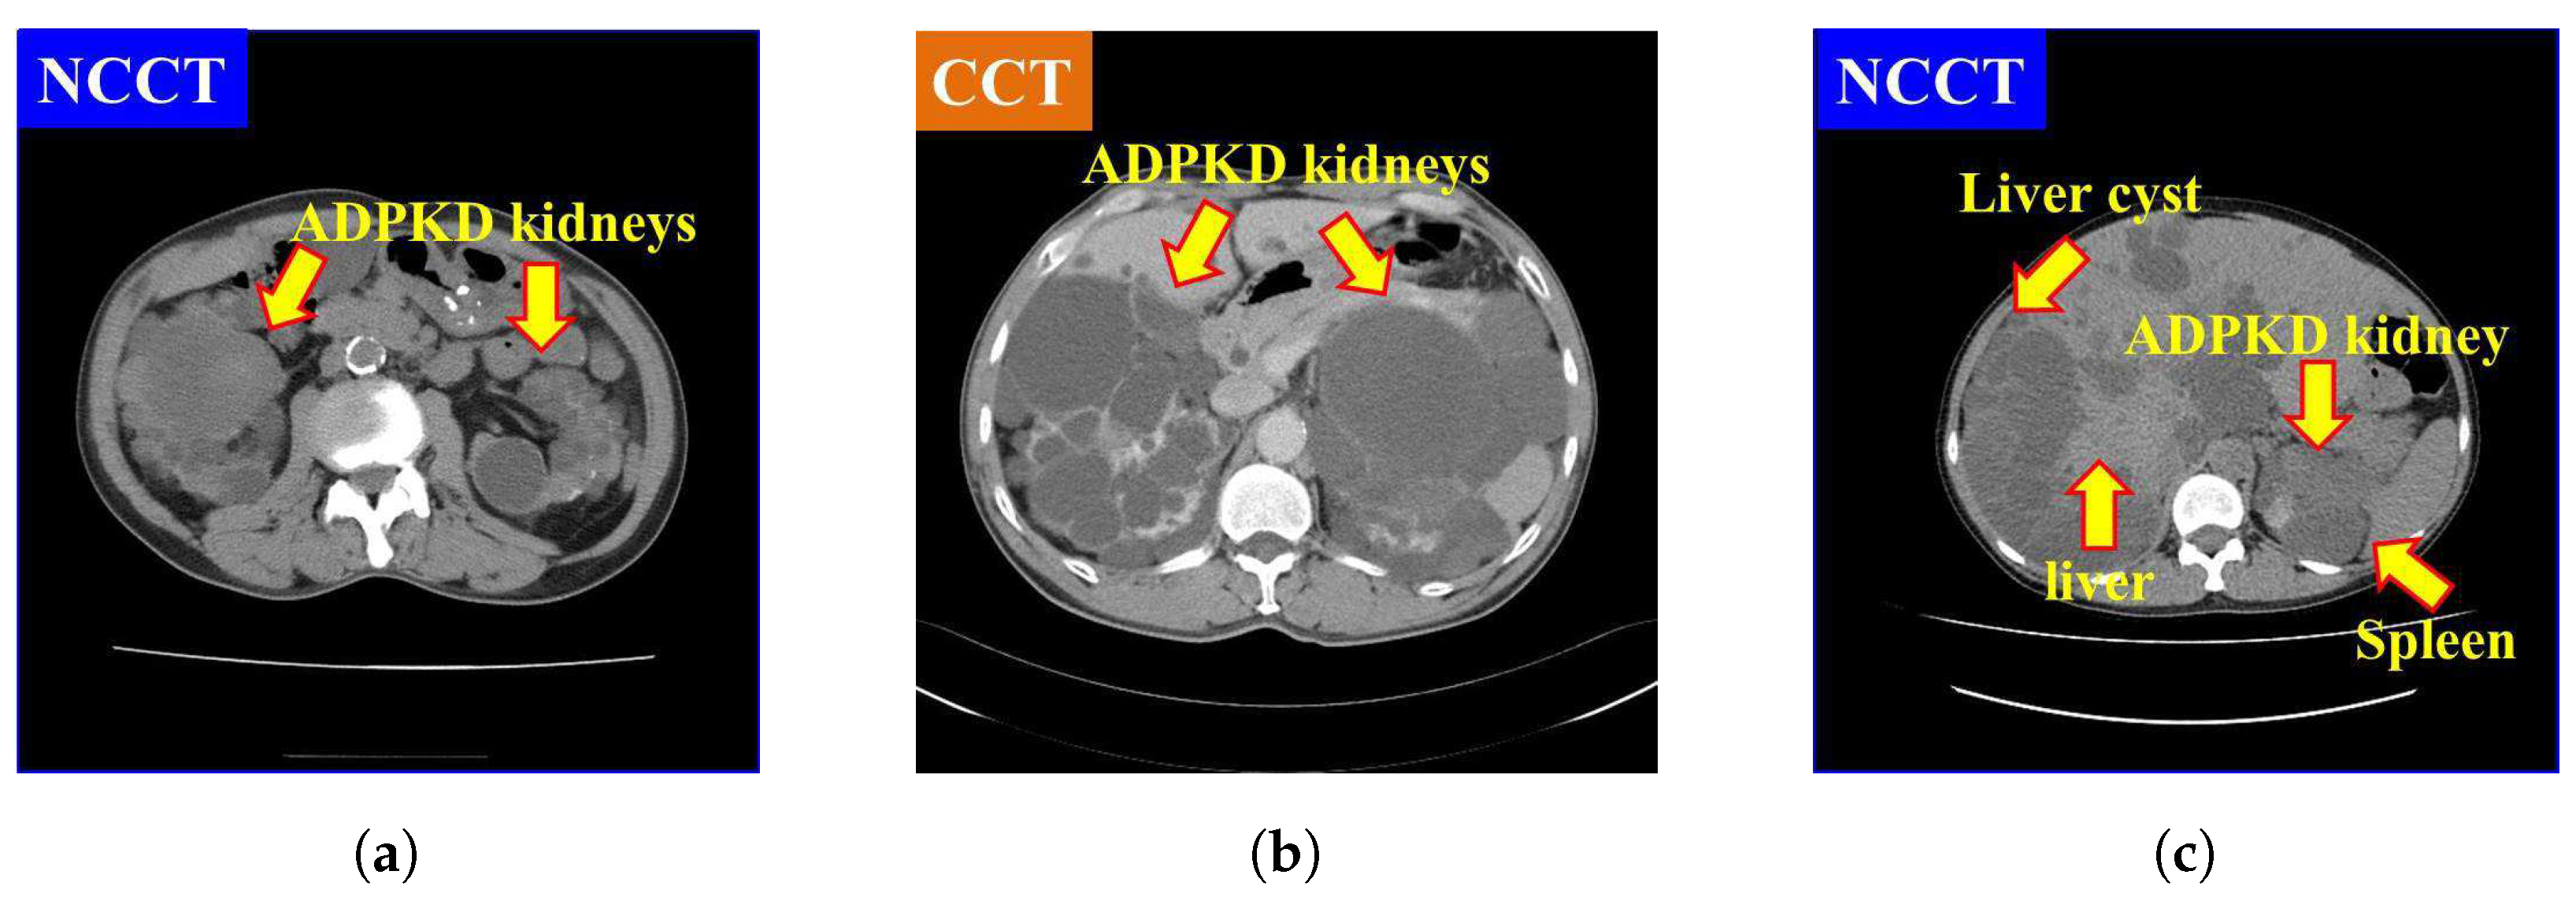

It is also found that NCCT images pose significant challenges for localization and segmentation due to several factors. First, the intensity of NCCT images, as shown in Figure 1a, is lower as compared to the CCT images, as illustrated in Figure 1b. Second, the intensity of liver cysts is similar to that of ADPKD kidneys, as shown in Figure 1c. Third, the intensity of ADPKD kidneys can be similar to adjacent organs such as the liver and spleen, as depicted in Figure 1c. This similarity makes it difficult to differentiate the boundaries of the ADPKD kidneys from neighboring organs during delineation. These limitations of NCCT in capturing detailed structural and functional characteristics of the kidneys can make tasks such as localization, segmentation, and TKV estimations difficult to perform accurately. As ADPKD is a progressive disease, cysts are often smaller and fewer in number during its early stage, which makes diagnosis through NCCT challenging. This difficulty arises because NCCT has limitations in accurately detecting and calculating the total number of cysts in the kidneys [29]. This is crucial in clinical practice as early diagnosis of ADPKD can lead to better patient prognosis. Therefore, incorporating NCCT and CCT for kidney localization, segmentation, and TKV estimation, using AI-based methods, can enhance diagnostic accuracy, improve early risk predictions, and ultimately optimize treatment strategies for better outcomes.

Figure 1. Comparison of NCCT and CCT for ADPKD kidneys: (a) ADPKD kidneys on NCCT. (b) ADPKD kidneys on CCT. (c) ADPKD kidney with adjacent organs such as liver and spleen, alongside liver cyst.

Based on our previously developed IP method for ADPKD using CCT [33], we apply four IP procedures to both NCCT and CCT images. First, image selection is performed by excluding images that do not contain both kidneys. Let R = { r 1 , r 2 , , r | R | } represent the set of selected raw image data in DICOM format (.Dcm). Each selected image r i , where i { 1 , 2 , , | R | } , is converted to Joint Photographic Experts Group (JPEG) format using RadiAnt DICOM Viewer software [34]. As shown in Figure 1a,b, both NCCT or CCT images exhibit significantly higher intensity values in the spine compared to other organs, including the ADPKD kidneys. To address this, we apply image enhancement techniques as the third preprocessing step to reduce the intensity variance. Global thresholding is then applied to adjust the coordinates or pixel intensities ( x , y ) of an image r i ( x , y ) . The image enhancement operation is expressed in Equation (1).